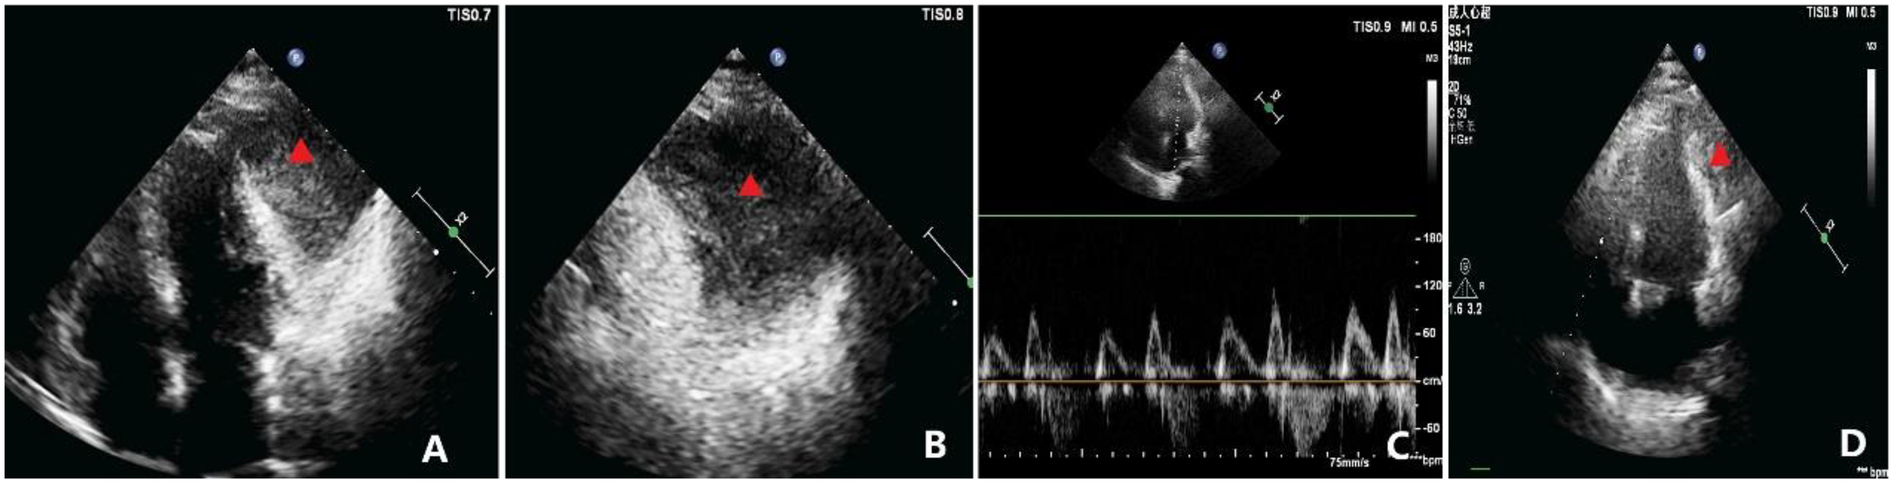

A 69-year-old woman presented with a 15-day history of chest tightness of unclear origin, which improved with rest but was accompanied by reduced activity tolerance. Chest CT (Figure 1) indicated localized thickening of the pericardium with a fluid-density shadow and a soft tissue-density lesion at the cardiac apex. Cardiac ultrasound (Figure 2) revealed left atrial enlargement and an echogenic mass (∼69 mm × 50 mm) in the pericardial cavity outside the anterior left ventricular wall. The lesion had relatively clear margins and was associated with slightly impaired ventricular wall motion, suggesting an extracardiac mass.

Figure 2

Echocardiographic findings. (A) Apical four-chamber view showing a homogenous mass, measuring approximately 69 × 50 mm, adjacent to the anterolateral wall of the left ventricle (indicated by the triangle), seemingly within the pericardial cavity. The mass is well-circumscribed, and the left ventricular anterolateral wall has mild hypokinesis. (B) Magnified view of (A) showing the relationship between the mass and adjacent structures in greater detail (indicated by the triangle). (C) Diastolic flow velocities across the mitral and tricuspid valves demonstrating significant respiratory variation, with the change in peak diastolic velocity during inspiration exceeding 30%. (D) Postoperative TTE apical view showing marked reduction in the residual mass burden compared with baseline (indicated by the triangle), with improvement in regional wall motion.